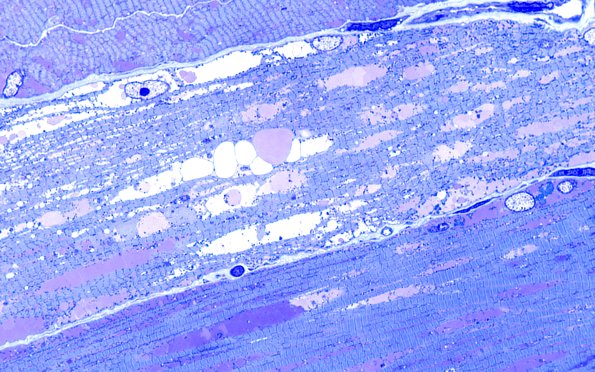

Washington University Experience | METABOLIC | Pompe Disease | 5C3 Muscle (Case 5) Plastic 100X 2

These longitudinal sections show pallor, distortion of the sarcomeres, vacuoles (undergoing various levels of content and extraction). (Plastic sections)